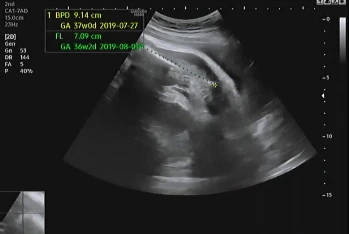

임신 39주 4일 차 병원에 내원해 초음파를 확인했다. 지난번에 이어 큰 이상이 없어 2주 뒤에 내원했는데 다행히 태아도 그동안 건강함을 알려주듯 초음파를 보는 내내 열심히 움직였다.

자궁경부의 길이는 지난번에 비해 얇아졌지만 여전히 아기는 골반에 위치하지 않고 위에서 놀고 있다고 했다. 자세를 잡은 지는 몇 주가 넘었지만 내려올 생각이 없이 열심히 놀기 바쁜 아기에게 얼른 내려오라고 이야기했는데 엄마의 말을 들어줄 생각이 없는 것 같다.